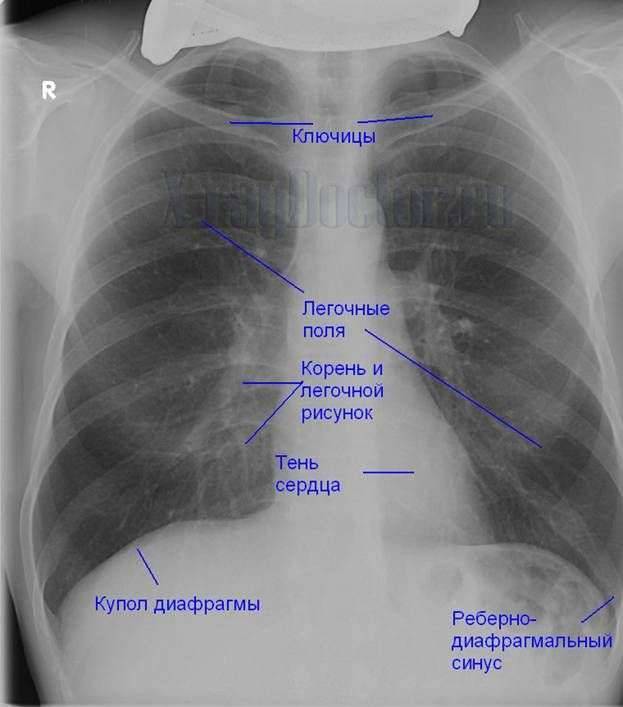

Фотографии, демонстрирующие обнаруженное усиление легочного рисунка

Раздел: Фотодневник открытий